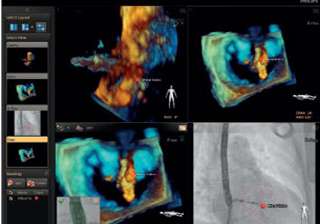

بعد تشخيص مريض بارتجاع الصمام الميترالي، ما هي خيارات العلاج المتوفرة له؟ إذا لم يكن مرشحًا للخضوع لعملية القلب المفتوح، يمكنك التفكير في معالجته عبر إصلاح الصمام الميترالي باستخدام القسطرة (TMVR). وفي يومنا الحالي، تؤمن حلول التصوير المبتكرة والأجهزة المتوفرة حديثًا خيارات جديدة لبعض المرضى.